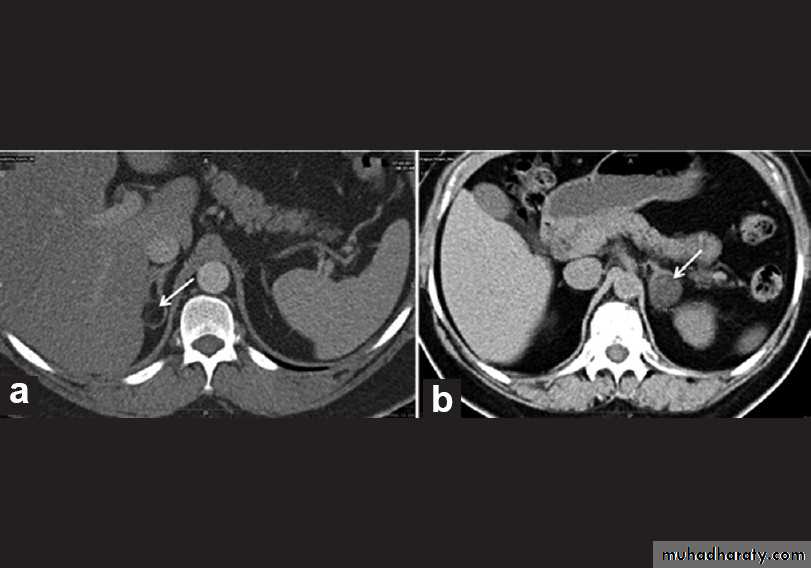

• CT features of a benign adrenal adenoma:

• Small size (<3 cm)

• Smooth contour

• Low density on unenhanced scans due to the high fat content of normal adrenal cells.

• CT features of adrenal carcinoma/metastasis include:

• Relatively large size (>5 cm)

• Higher density on unenhanced scans with low density centrally due to necrosis

• Other evidence of malignancy, such as liver metastases, lymphadenopathy, venous invasion.

• Equivocal lesions may be further assessed with multiphase contrast-enhanced CT. Attenuation value of the adrenal mass is measured pre-contrast injection and then at 60 seconds and 15 minutes after injection.

• Adrenal adenomas show rapid enhancement and subsequent washout with intravenous contrast material (Adrenal adenoma will show low attenuation pre-contrast, high attenuation at 60 seconds, and significantly reduced attenuation at 15 minutes).